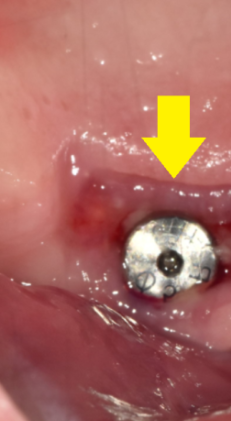

잇몸을 보면 이런 모습입니다!!

230531

힐링이 빠짐과 동시에

빠른 속도로 잇몸이 닫힙니다ㅠㅠ